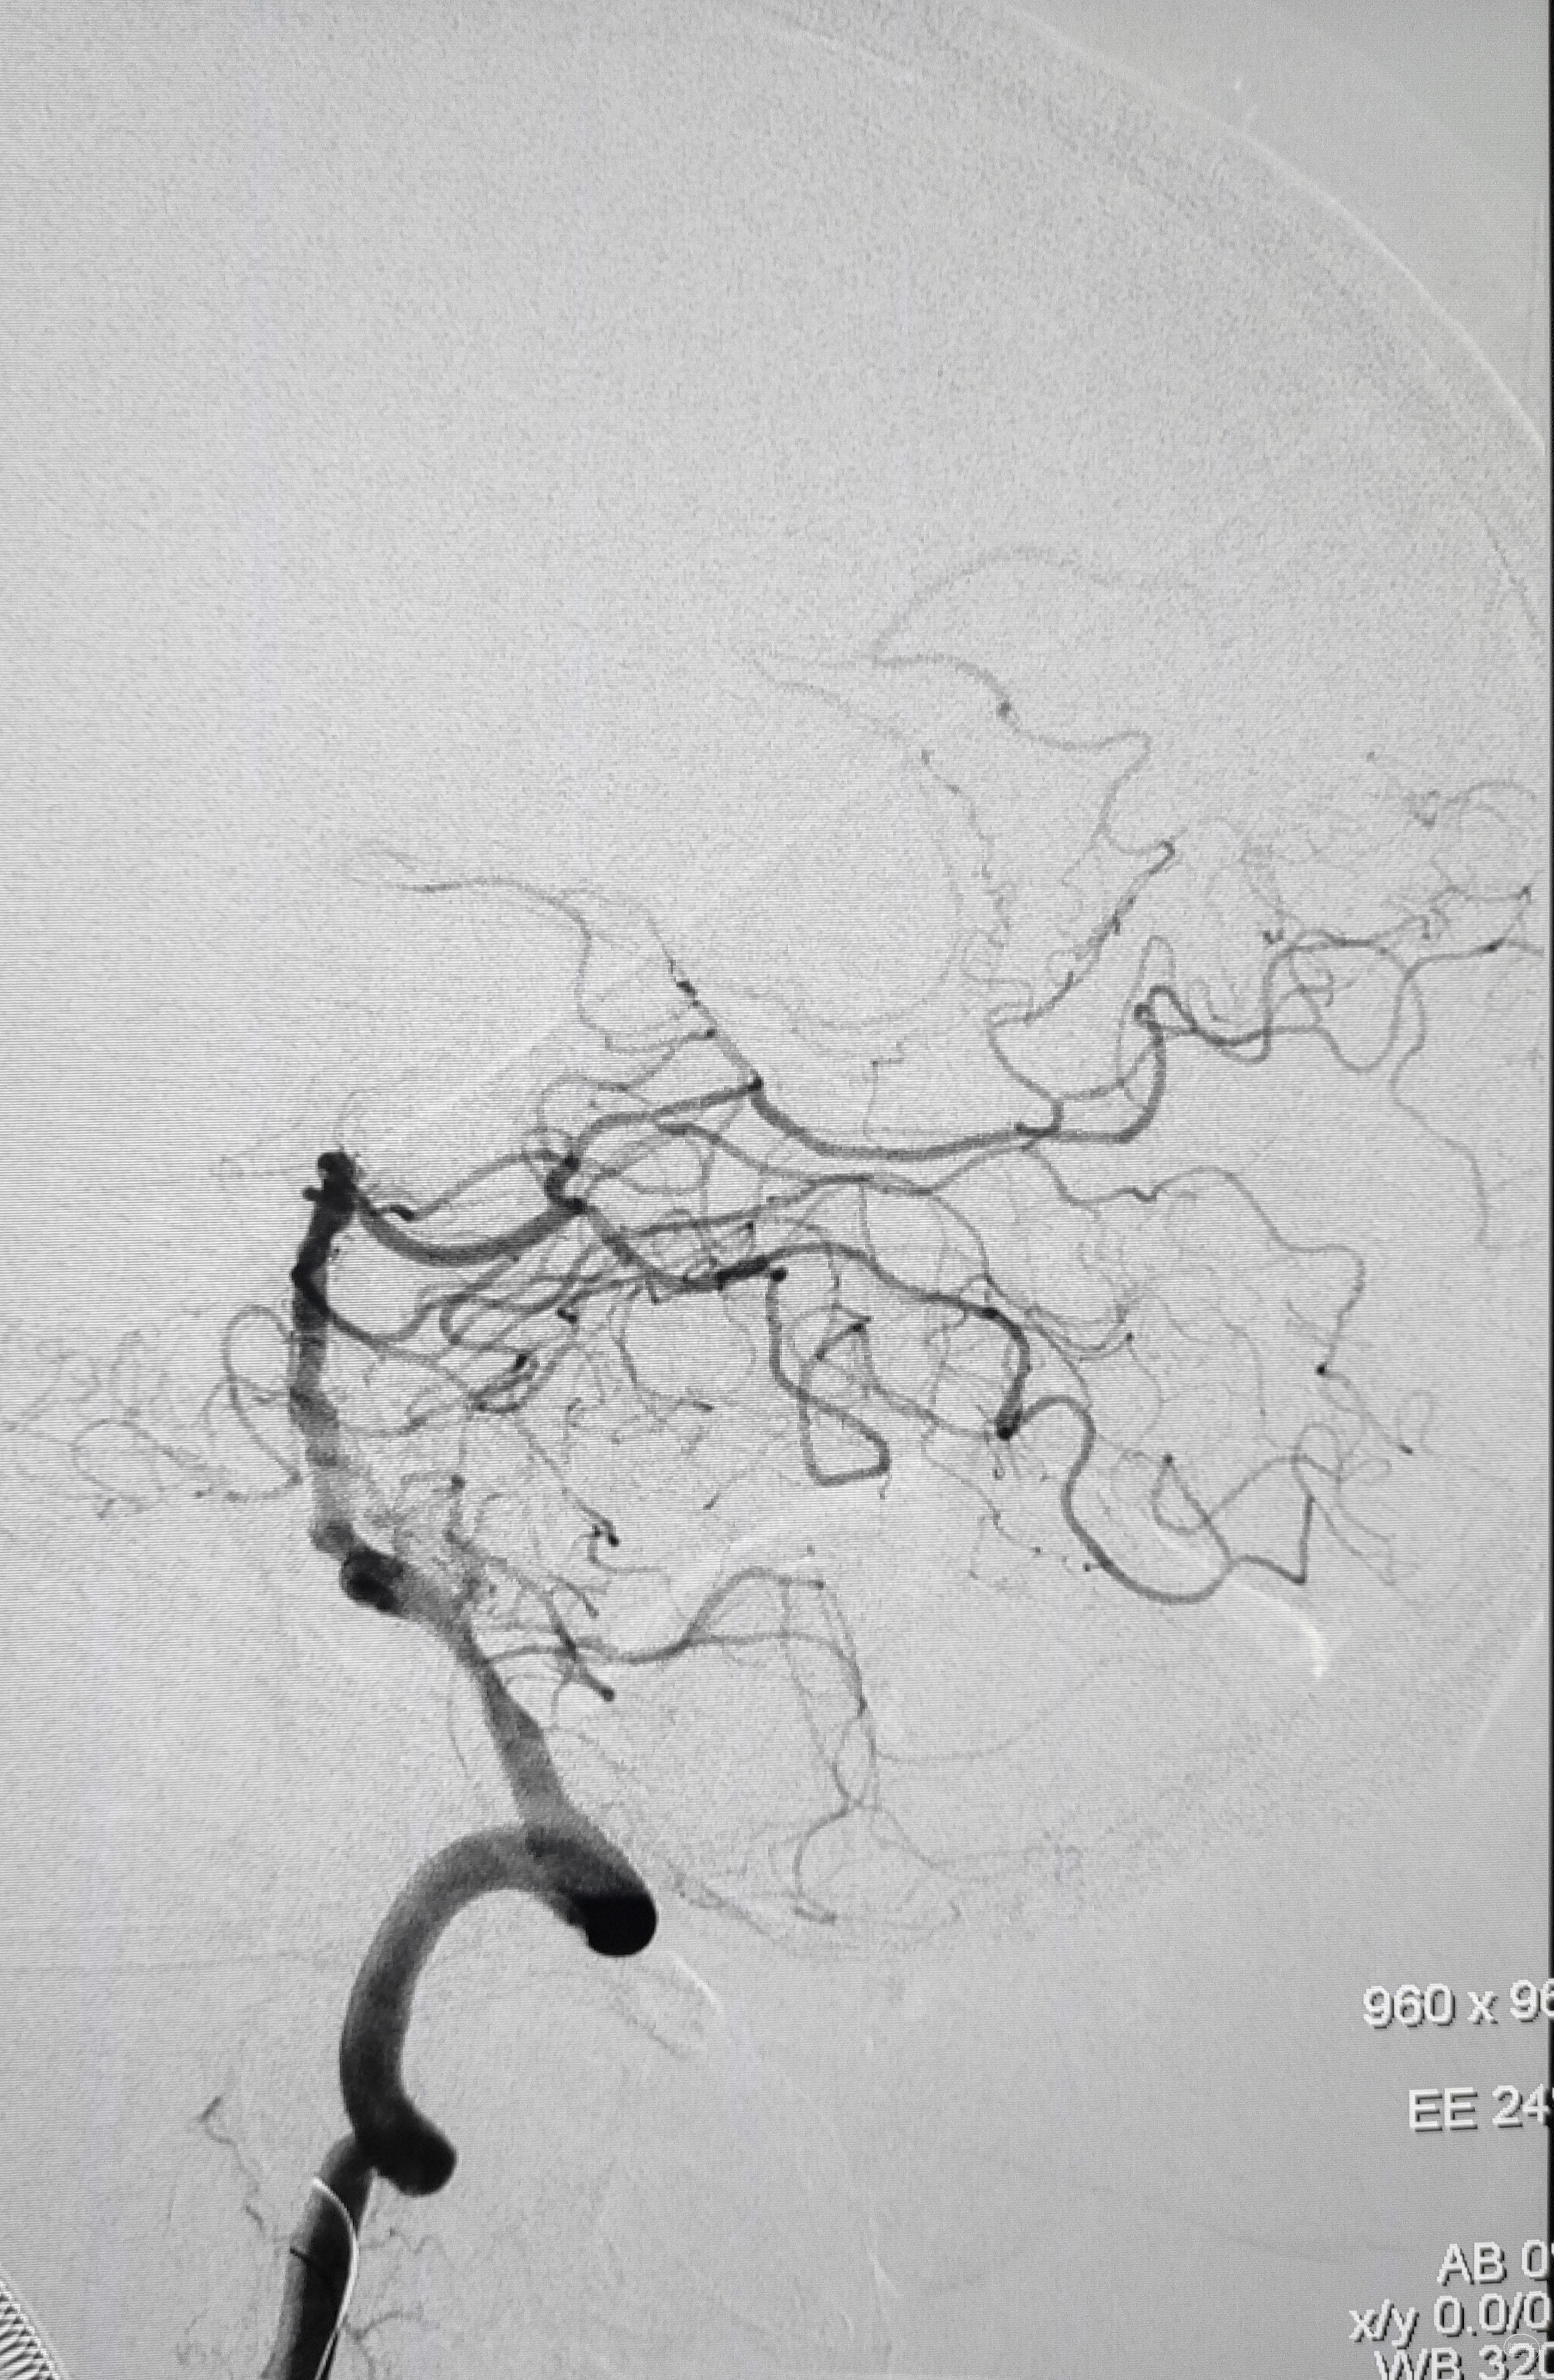

右侧颈总动脉正侧位造影:意料之外的是,枕动脉通过肌支与右侧椎动脉吻合(紫色箭头),像极了《大风吹》的歌词“借一杯天上的水”,源源不断进行着血流的补充。但是好景不长,同侧V4段明显狭窄,无情的设置了第二道坎(绿色箭头)。

左侧颈总动脉造影:颅内床突段以远基本闭塞,仅残涓涓细流,血供极差,脑膜中动脉瘤仅少量代偿,确实不容易,这估计就是想来搭桥的初衷了吧。